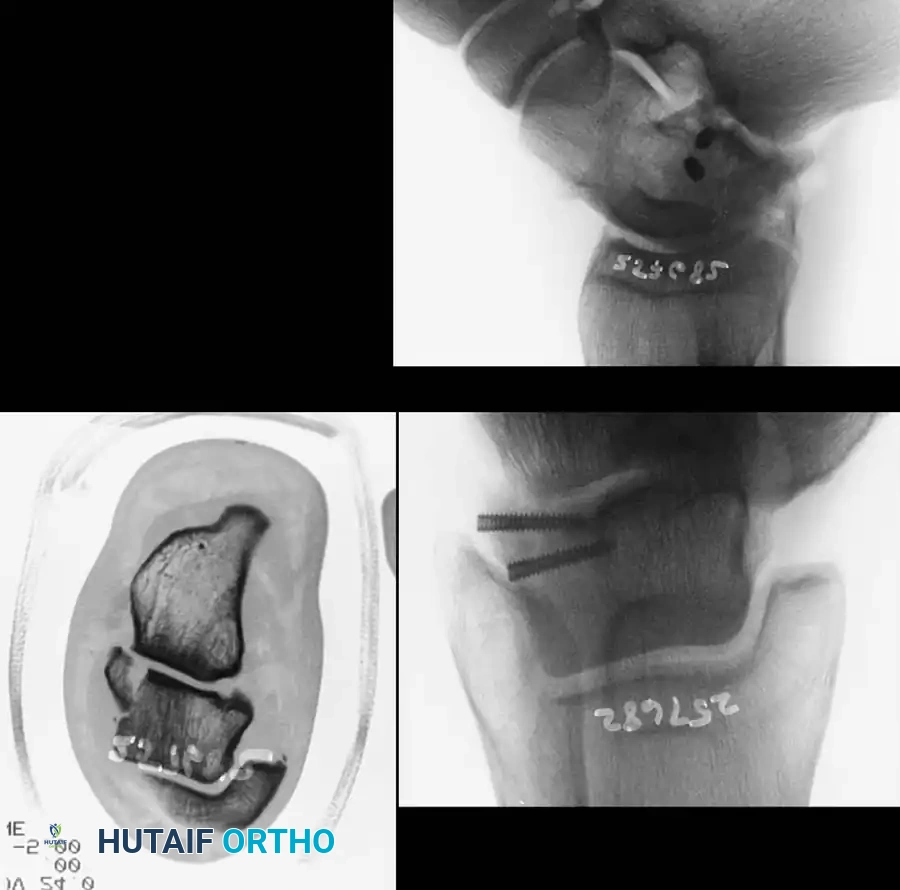

Reduction and Fixation:

Once anatomically reduced, provisional fixation is achieved with K-wires. Definitive fixation typically involves multiple lag screws (3.5 mm or 4.0 mm) placed from anterior to posterior, or posterior to anterior.

Fixation X-ray 1

Fixation X-ray 2

Posterior-to-anterior screw placement (via a posterolateral approach) is biomechanically superior as it engages the denser bone of the talar head, but it requires careful avoidance of the flexor hallucis longus (FHL) and the neurovascular bundle.

Post-op fixation 1

Post-op fixation 2

In cases of severe medial comminution, a mini-fragment plate (e.g., 2.0 mm or 2.4 mm) may be applied to the medial talar neck to act as a buttress and maintain length, preventing varus collapse.